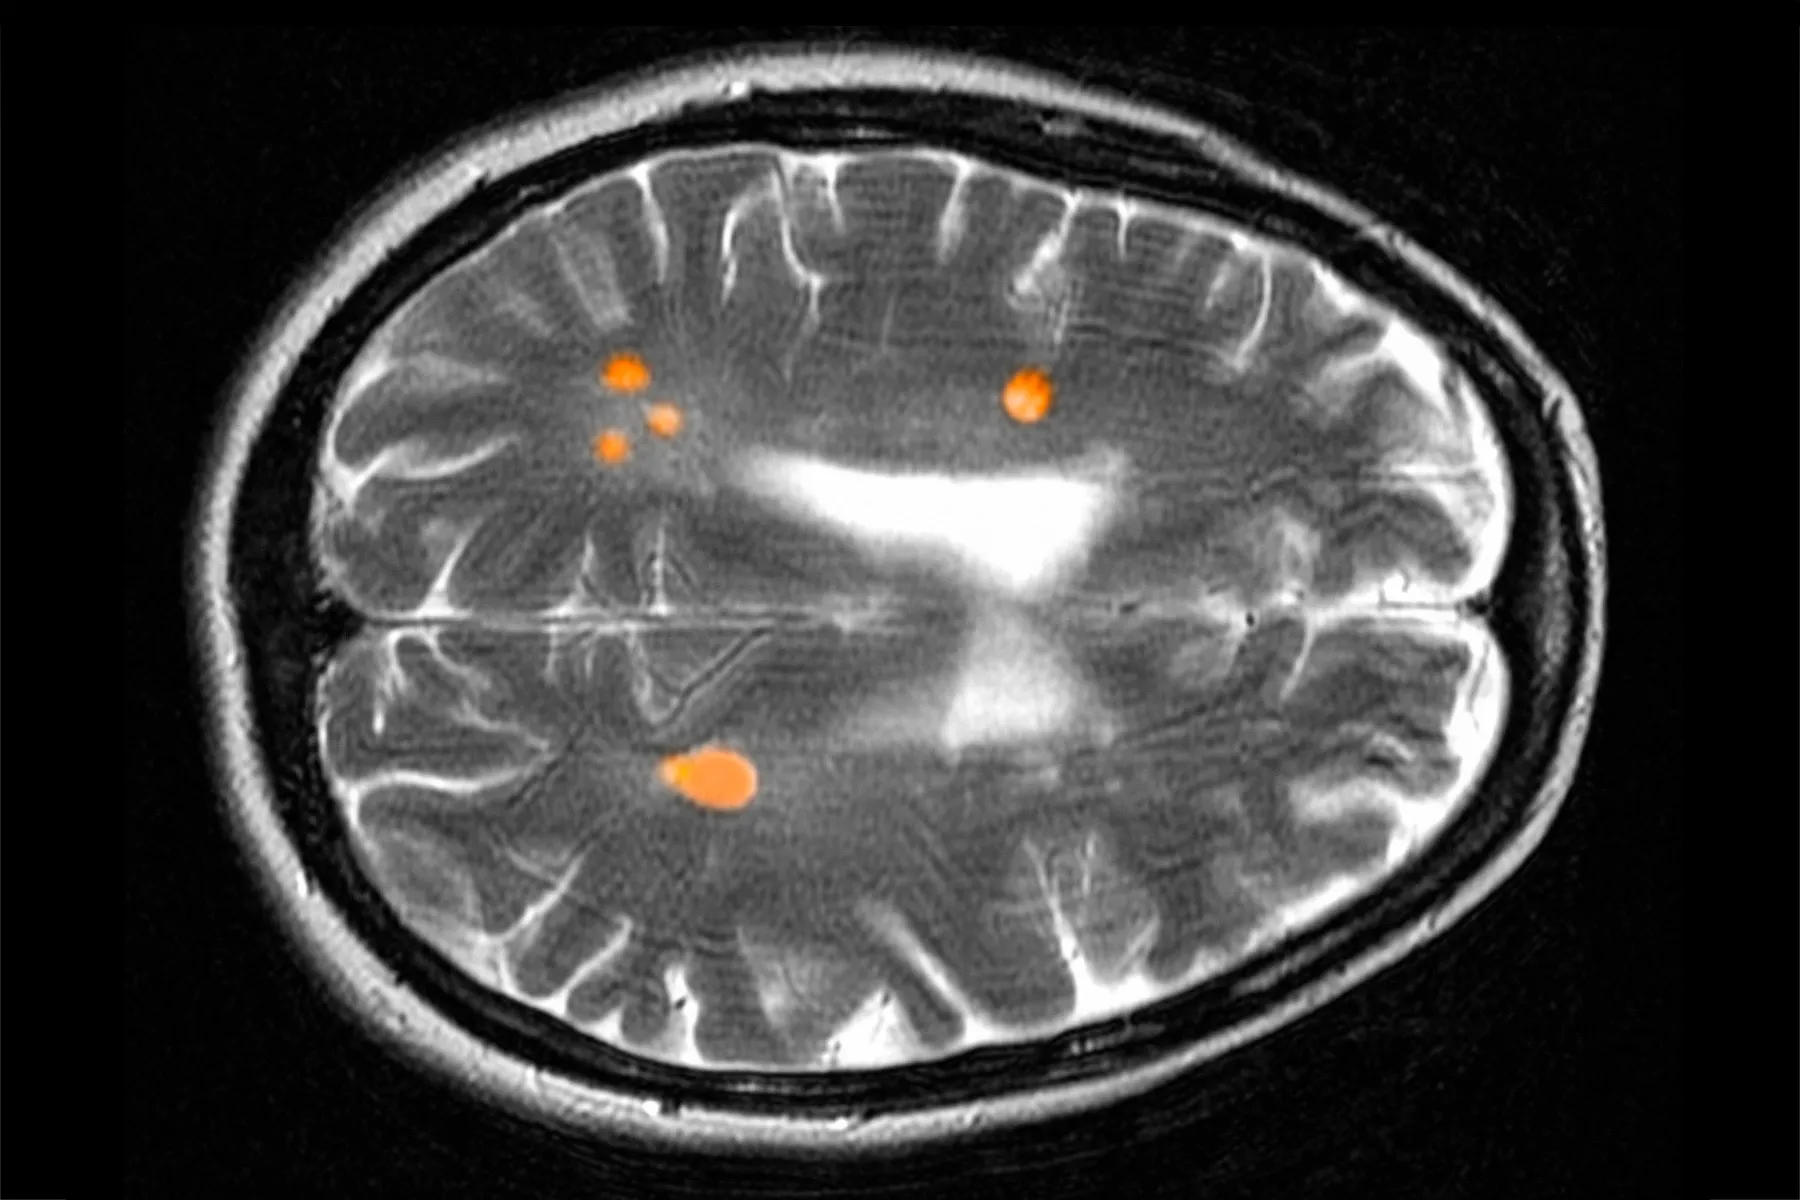

Aproximativ un milion de americani trăiesc cu esclerosis multiplă progresivă, o boală autoimună care atacă sistemul nervos central și poate duce la o deteriorare progresivă, variind de la probleme de memorie și gândire până la slăbiciune musculară și dificultăți de mobilitate. Causa este necunoscută, dar probabil implică factori genetici și de mediu. De obicei, boala începe cu recidive – flare-uri bruşte când sistemul imunitar devine hiperactiv și „atacă o zonă nouă din creier sau măduva spinării.” Fiecare atac lasă o nouă cicatrice și produce noi simptome.

În prezent, tratamentele de bază pentru formele recidivante de esclerosis multiplă sunt terapiile modificatoare ale bolii (DMT-uri). Acestea funcționează în moduri diferite, dar efectul comun este acela de a reduce inflamația care determină recidivele. Totuși, acestea sunt limitate în capacitatea de a acționa direct asupra celulelor imune implicate în procesul de deteriorare a nervilor. Astfel, au relevat un factor mai subtil care contribuie la dizabilitatea pe termen lung: neuroinflamația lentă, care este în mare parte independentă de recidive și alimentează deteriorarea nervilor în nrSPMS.

Pacienții cu nrSPMS sunt „de obicei tratați cu DMT-uri doar pentru a preveni orice recidive suplimentare care pot contribui la o dizabilitate suplimentară,” a spus Kornberg. Dar beneficiile sunt limitate, iar pentru o persoană cu esclerosis multiplă progresivă, este o cursă între eficiența modestă a DMT-ului și momentum-ul necontrolat al deteriorării nervoase subiacente. Aici intervine tolebrutinib. Spre deosebire de tratamentele existente pentru esclerosis multiplă, noul medicament este o moleculă mică concepută pentru a trece prin bariera sânge-creier, o membrană selectivă care protejează sistemul nervos central de toxine și agenți patogeni din sânge. Aceasta permite tolebrutinibului să pătrundă în creier și în măduva spinării, unde are loc deteriorarea pe termen lung în esclerosis multipla, încetinind declinul necruțător cauzat de boală.

Tolebrutinib, dezvoltat de compania biotech Principia Biopharma înainte de a fi achiziționat de Sanofi în 2017, vizează sistemul nervos central. Acolo, inhibă o enzimă numită kinaza tirozinei Bruton’s (BTK), o proteină exprimată în celulele imune din creier și măduva spinării. Aceste celule imune, sau microglia, devin hiperactive la pacienții cu esclerosis multiplă, eliberând proteine numite citokine care declanșează inflamație extinsă, atrăgând celule imune agresive din sânge în creier. De asemenea, ele distrug mielina, teaca protectoare care izolează fibrele nervoase și asigură o comunicare corespunzătoare între creier și corp. Când mielina se degradează, pacienții experimentează oboseală, rigiditate musculară, slăbiciune și pierderea coordonării, printre alte simptome. „Ceea ce este diferit în cazul tolebrutinibului și altor inhibitori BTK care pătrund în creier este că poate opri acele microglia inflamate,” a spus Kornberg. „Aceasta este motivele pentru care are un efect asupra progresiei.”